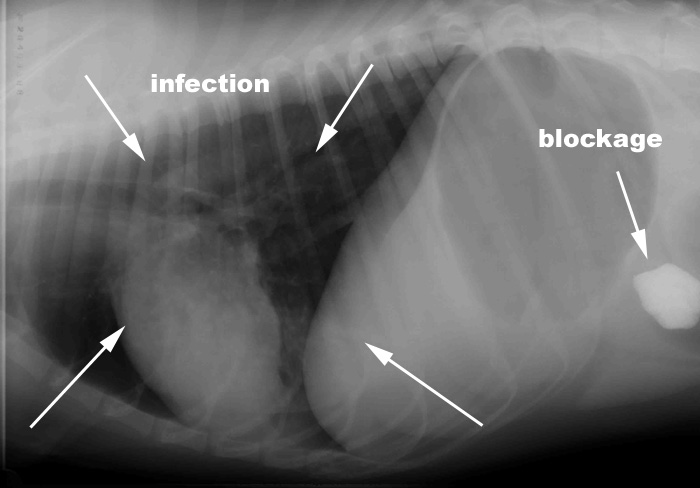

James' Lungs: as you can see there is some infection in his lungs, as evidenced by the cloudiness in the lungs.  Off to the right you can see the rock in his intestines.

James' Chest:  Lungs look cloudy, this is  pneumonia which according to culture, is caused by 2 different bacteria so he is on 2 different antibiotics to fight it.  The small rice-shaped white spot is actually his microchip.